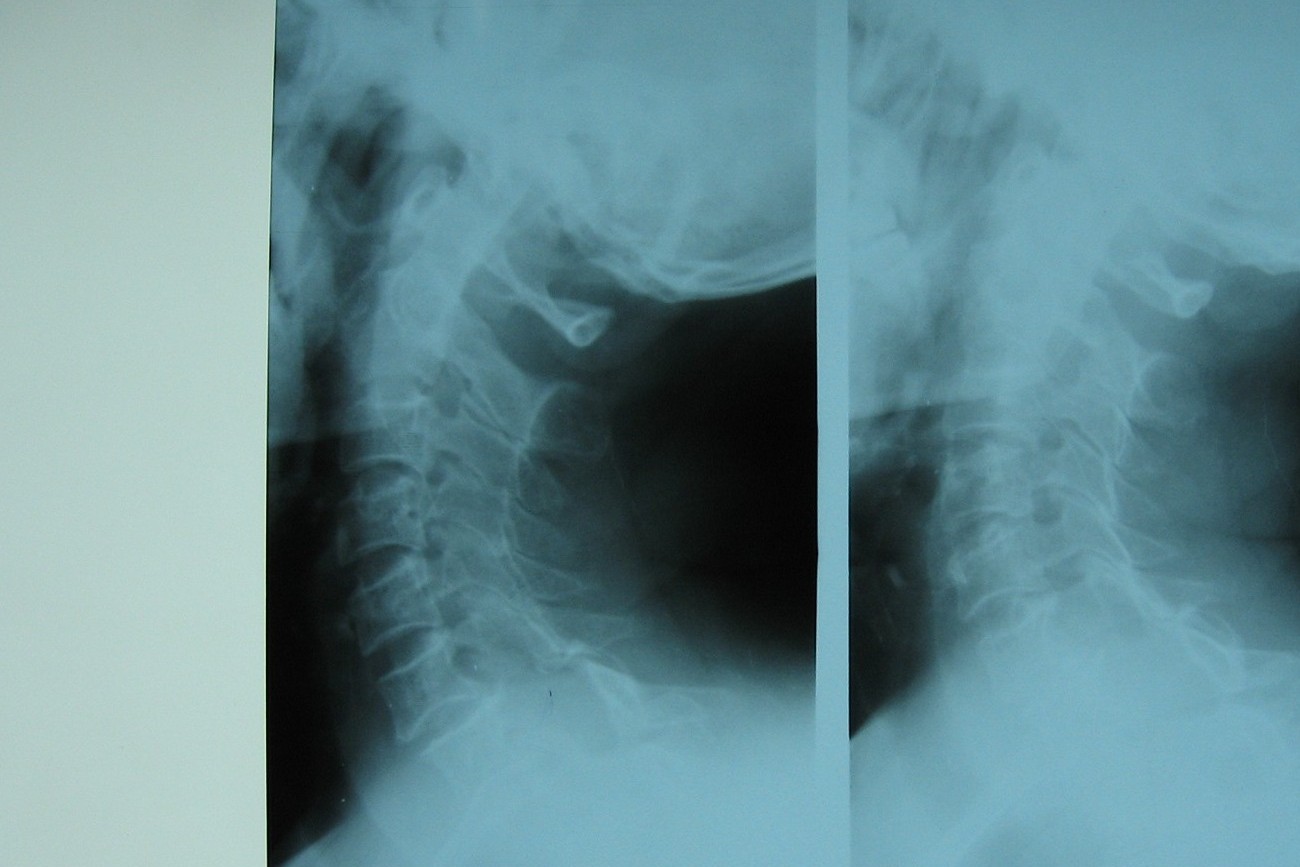

标题: CT7396:病人女65岁主因颈部肿疼伴上肢麻木4年近来加重入院 [打印本页]

标题: CT7396:病人女65岁主因颈部肿疼伴上肢麻木4年近来加重入院

支持考虑:神经原性肿瘤。(右侧椎间孔扩大,椎板破坏,局部明显的软组织肿块,并与椎管 神经根关系密切。)

支持考虑:神经源性肿瘤(右侧椎间孔扩大,椎板破坏,局部明显的软组织肿块,并与椎管神经根关系密切)。